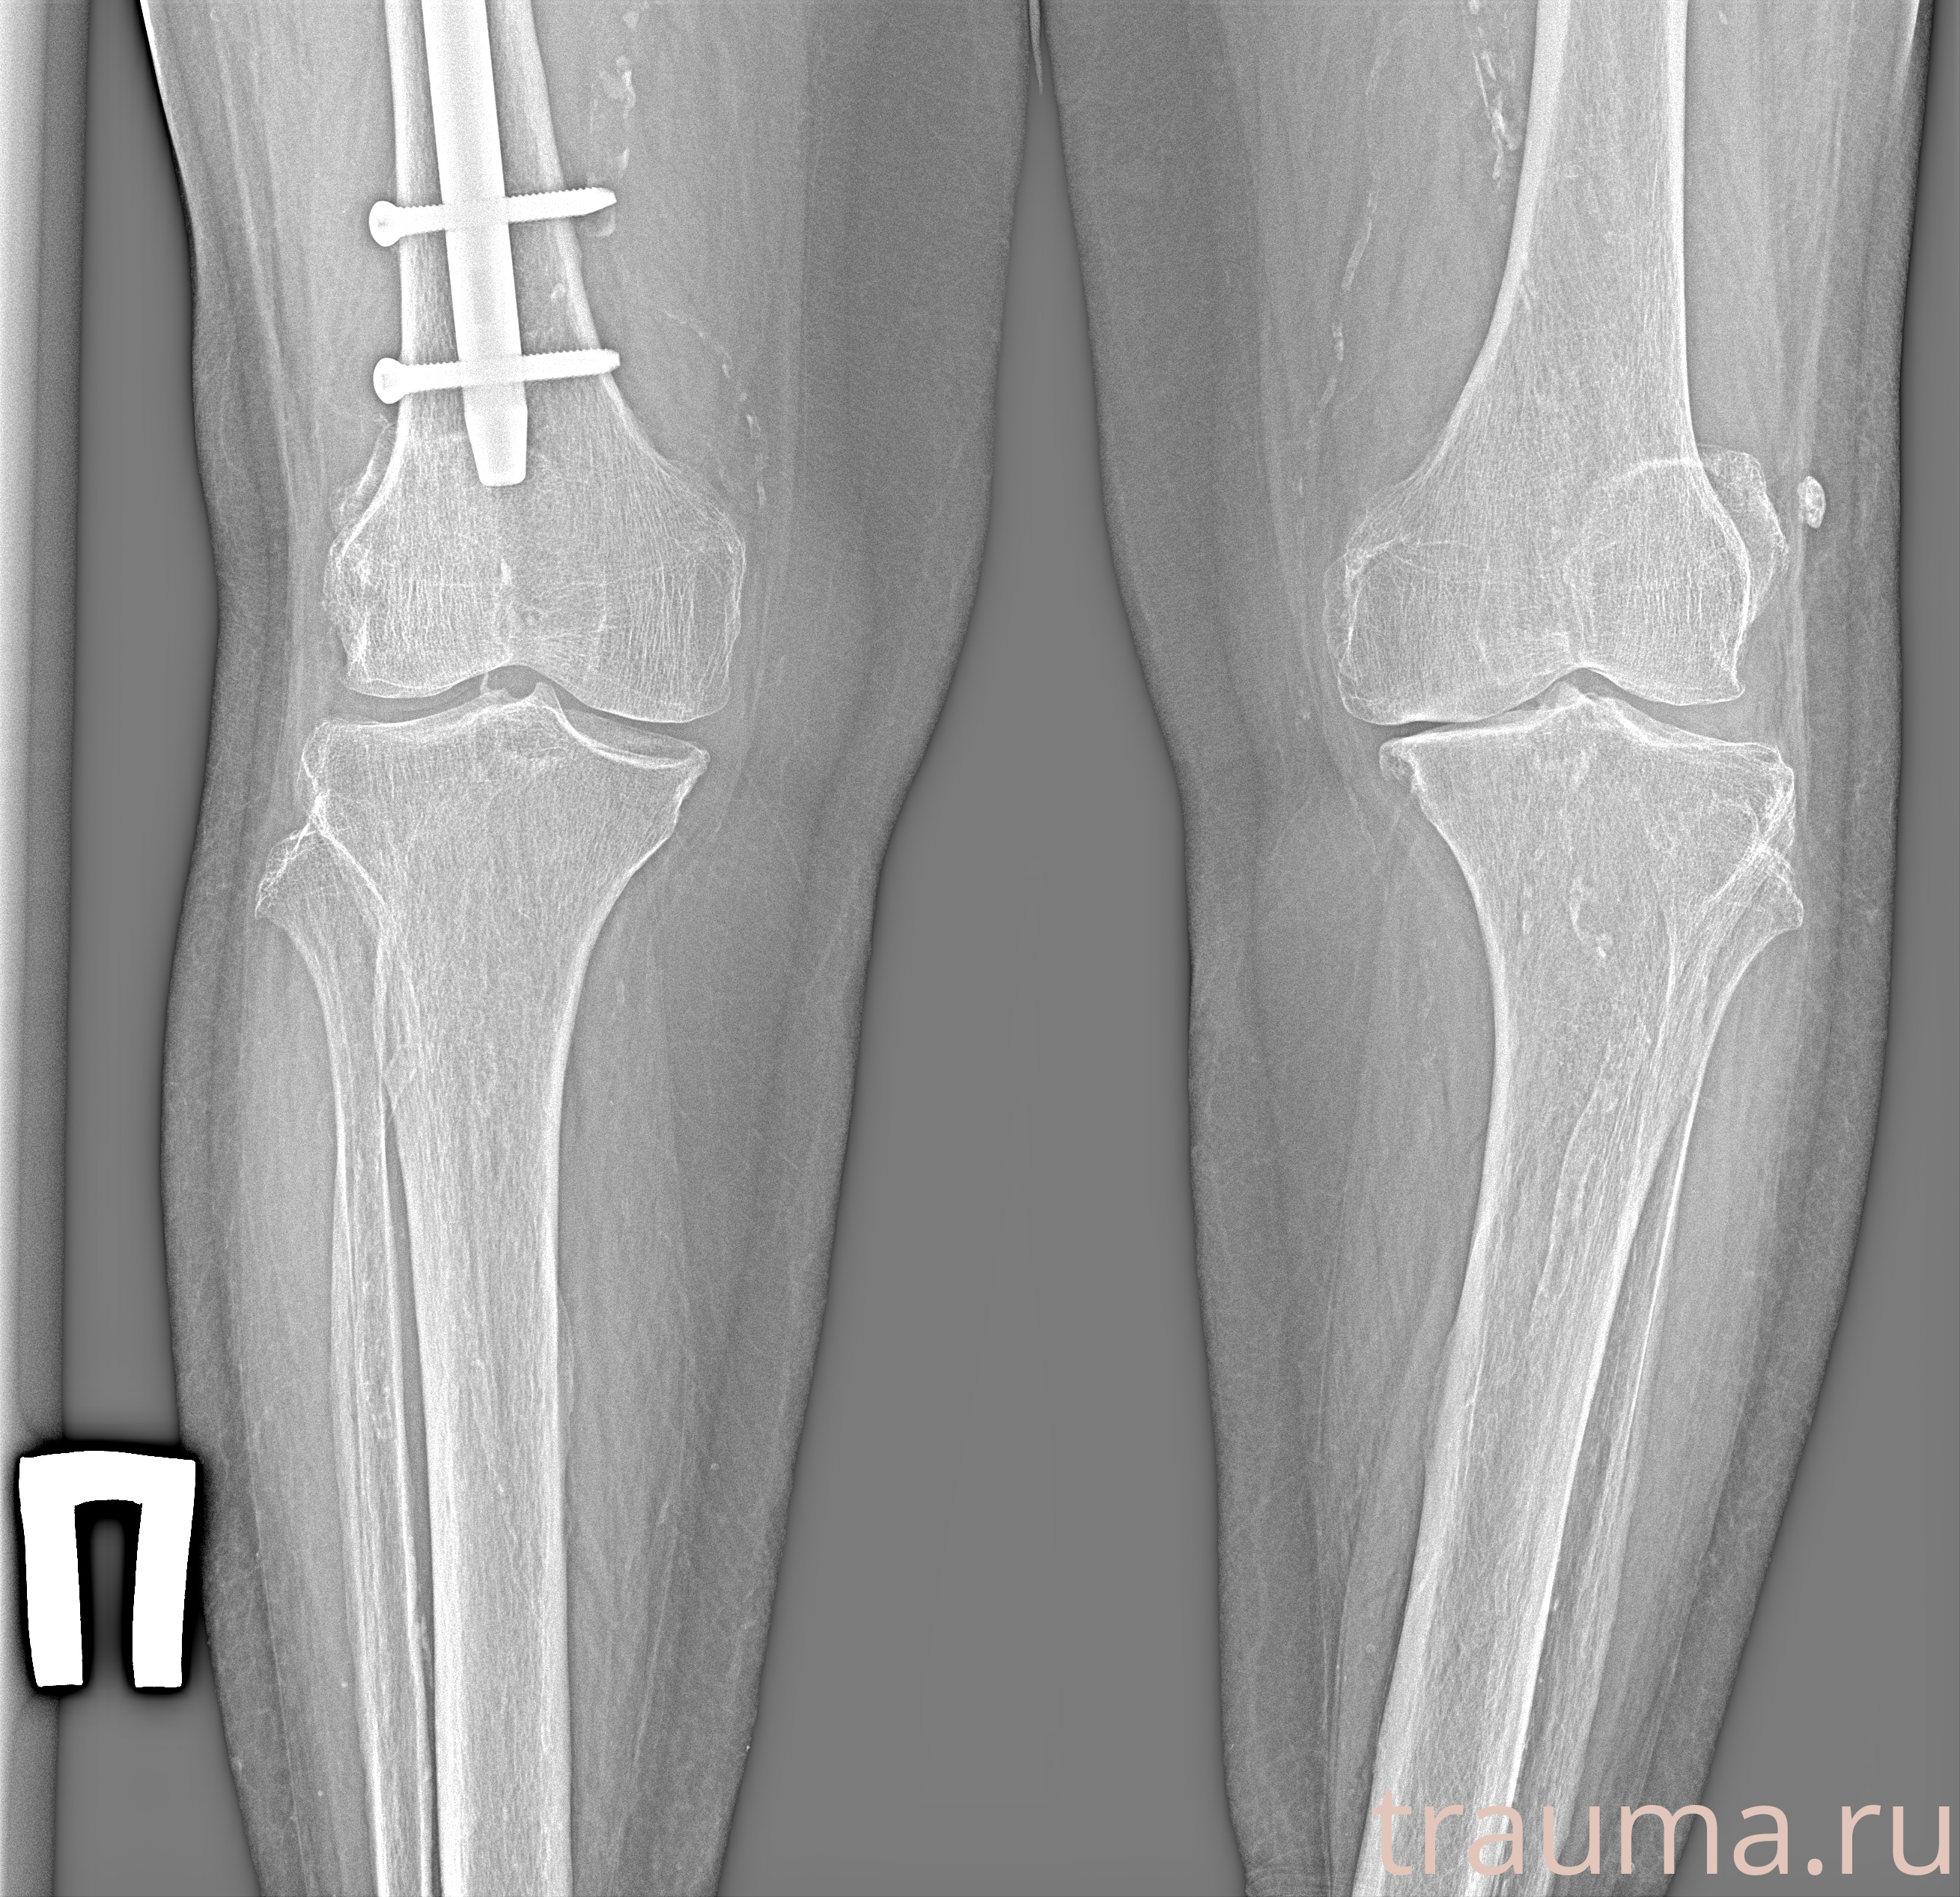

Рентгенограммы

Рентген на дому: по вашему адресу приезжает врач-рентгенолог, травматолог-ортопед с мобильным рентгеновским аппаратом, проводит диагностику травмы или заболевания, делает необходимые рентгенограммы, дает рекомендации по дальнейшему лечению. Получить качественные снимки в домашних условиях возможно благодаря уникальной методике, разработанной МосРентген Центром для института  Склифосовского